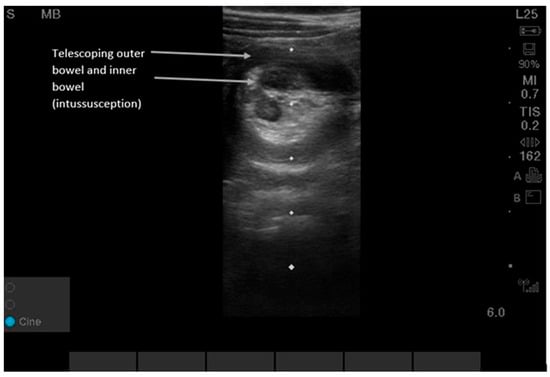

Figure 5.

Intussusception can be detected by either the lawnmower or the point-of-maximal-pain technique. Users can begin in the right upper quadrant since this is the most common location (80% of intussusceptions are ileo-colonic) and then scan along the entire colon in the peripheral abdominal wall area using a “picture-frame” technique [23,24,25,26]. Supplementary Video S5 shows dynamic findings. POCUS shows a “target-shaped” or “donut-shaped” mass > 2 cm, with telescoping of one section of bowel into the adjacent bowel. Sensitivity and specificity for POCUS were 96.6% (95% CI, 82.2, 99.1) and 98% (95% CI 96.5, 99.9) in pediatric patients aged three months to six years old at 17 pediatric EDs in North and Central America, Europe, and Australia between 2018 and 2020 [23,24,25,26]. While the classic ‘target sign’ is consistent, intussusception in adults is frequently pathologic and requires identification of a potential lead-point mass, differing from the often idiopathic pediatric presentation [23,24,25,26].